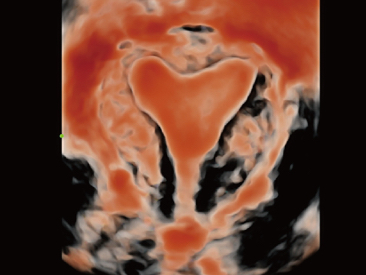

As well as the premium level image quality, Resona 7 also enhances clinical research capabilities with the revolutionary V Flow for vascular hemodynamic evaluation, and the most intelligent plane acquisition from 3D datasets for fetal CNS diagnosis. Combining the most intuitive gesture-based multi-touch operation and all the essential clinical features, Resona 7 is truly leading new waves in ultrasound innovation.